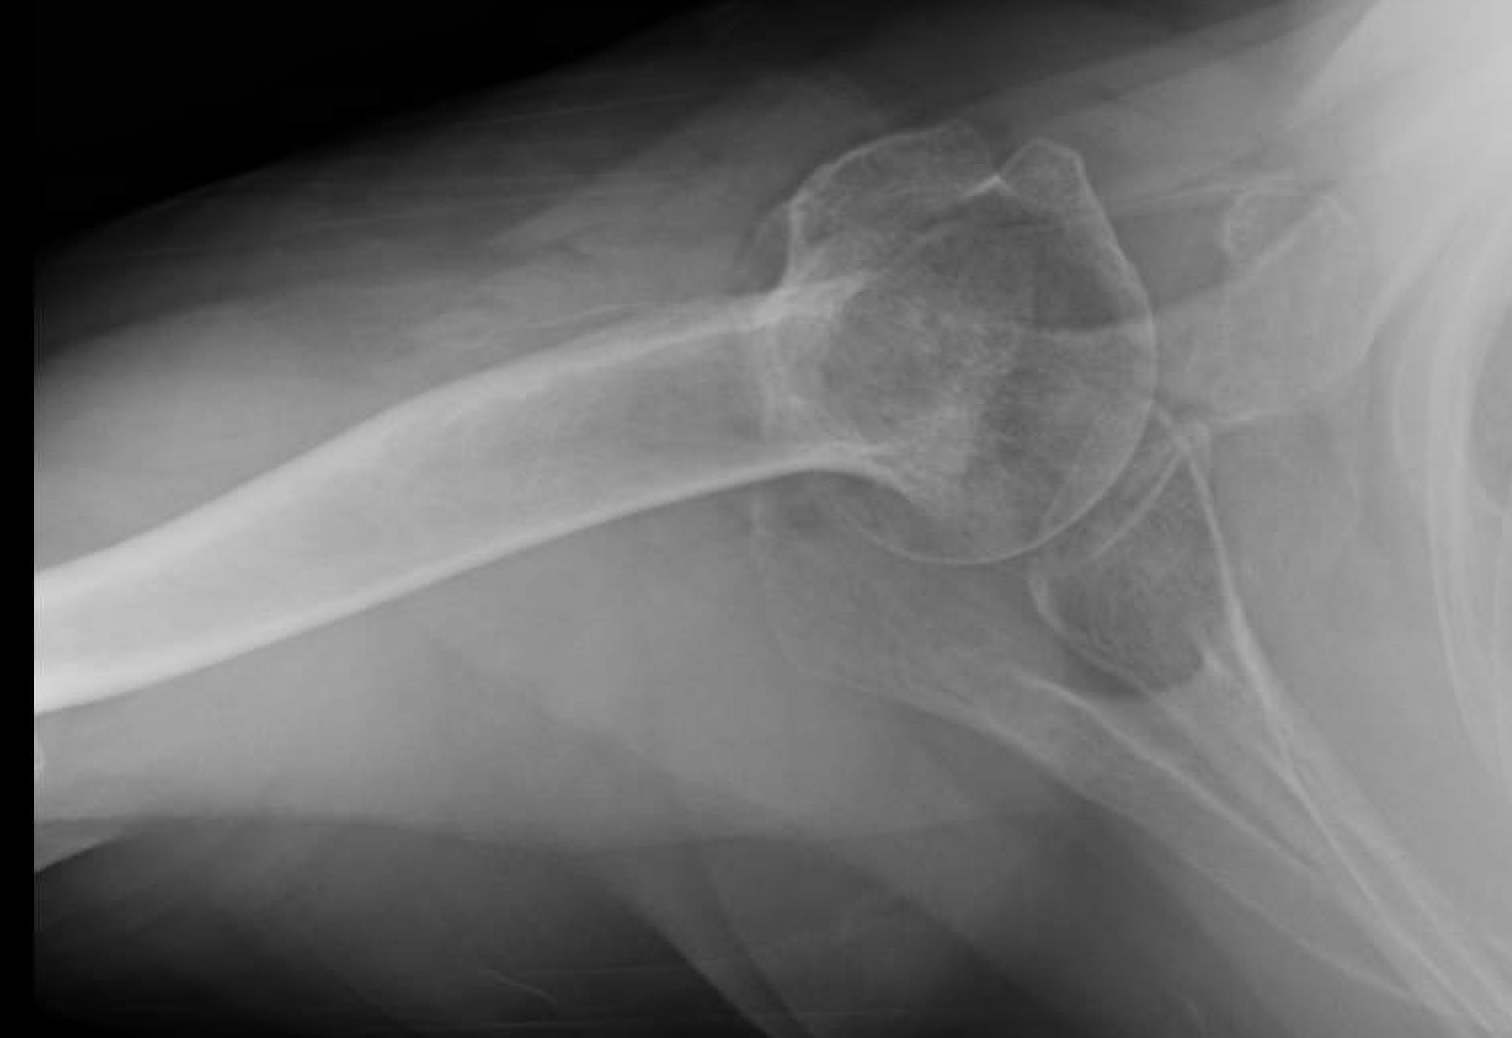

Treating a Proximal Humerus Fracture Elbow Fracture Non Operative Protocol Rehabilitation protocol nonoperative radial head fracture. • protocol must be altered based on fixation strength at. The following guidelines for stable elbow fractures and simple dislocations. • continue to control pain and edema as needed •. Rom by end of 2nd week should be at least 15 to 115. Passive and active elbow rom as tolerated: This protocol is recommended. Elbow Fracture Non Operative Protocol.